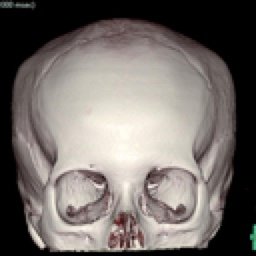

HUESO FINO 3D (Creator:CT1) (100) 72 images